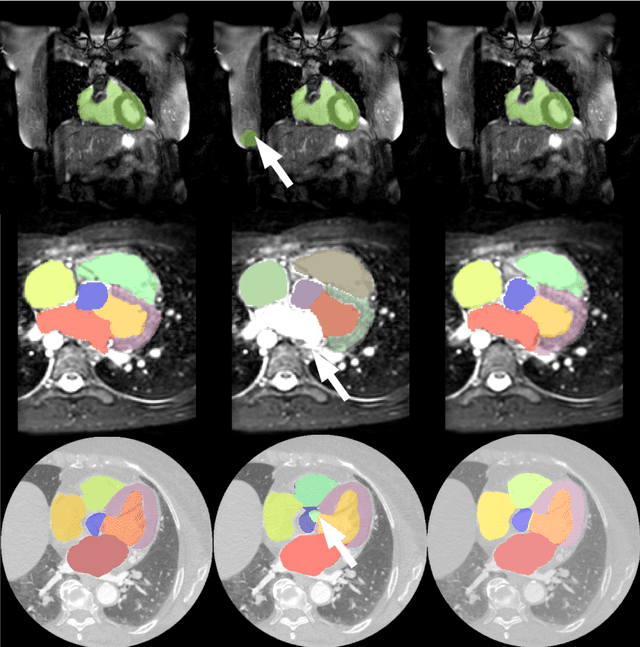

Abstract:Deep convolutional neural networks (CNNs) have been intensively used for multi-class segmentation of data from different modalities and achieved state-of-the-art performances. However, a common problem when dealing with large, high resolution 3D data is that the volumes input into the deep CNNs has to be either cropped or downsampled due to limited memory capacity of computing devices. These operations lead to loss of resolution and increment of class imbalance in the input data batches, which can downgrade the performances of segmentation algorithms. Inspired by the architecture of image super-resolution CNN (SRCNN) and self-normalization network (SNN), we developed a two-stage modified Unet framework that simultaneously learns to detect a ROI within the full volume and to classify voxels without losing the original resolution. Experiments on a variety of multi-modal volumes demonstrated that, when trained with a simply weighted dice coefficients and our customized learning procedure, this framework shows better segmentation performances than state-of-the-art Deep CNNs with advanced similarity metrics.